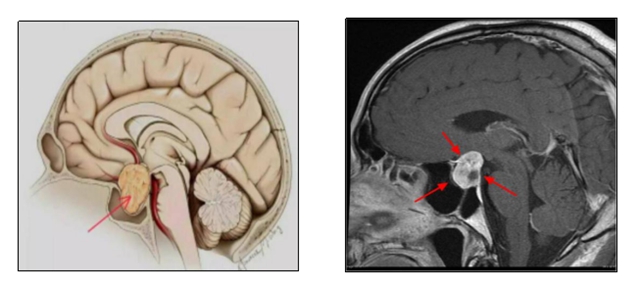

孩子生长发育异常,建议可以给孩子做个头颅磁共振检查,看看脑垂体是否异常。

什么是脑垂体?

脑垂体,呈卵圆形是颅脑里一个重要的器官是人体最为复杂的内分泌腺。

分泌多种激素如生长激素、泌乳素促性腺激素等。

这些激素对人体代谢生长、发育和生殖等都有重要作用。

垂体正常:人体生长发育正常,身高正常生长。

垂体异常:可能影响人体身高发育,还可能引起异常泌乳、女性月经不调、视力下降等症状!

垂体腺瘤

垂体腺瘤有可能引起人体生长过快成为巨人症,也可能引起人体身材矮小成为侏儒症。

磁共振是一种新兴的高端影像检查技术,具有无创伤,无辐射,软组织分辨力高等优势,是目前检查垂体最好的方法,可以全方位显示垂体形态、信号,从而判断正常或异常!